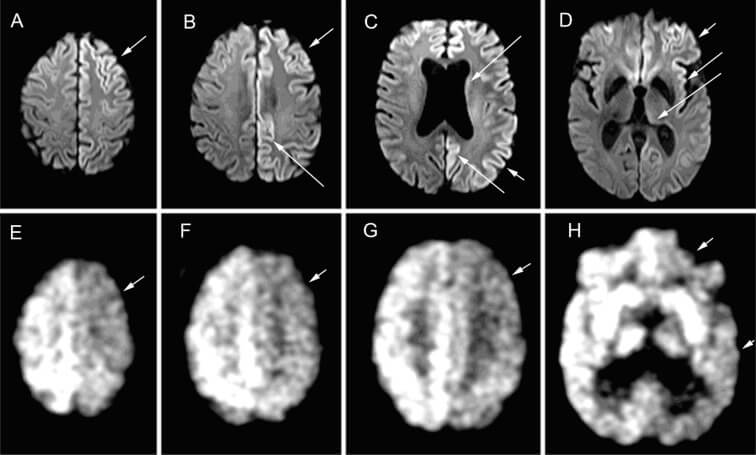

А это именно те проблемы, о которых так часто сообщают люди, столкнувшиеся с «долгим ковидом». Интересно, что ряд недавно опубликованных исследований также представил дополнительные доказательства нейронной инфекции во время COVID-19: с помощью ЭЭГ исследователям удалось измерить, насколько хорошо функционирует мозг с точки зрения его электрических сигналов.

В исследовании принял участие всего 41 пациент с положительным тестом на коронавирус и 14 других пациентов, у которых наблюдались некоторые симптомы, но в конечном итоге результат теста был отрицательным. Все испытуемые переносили болезнь в легкой форме и не были госпитализированы. Полученные результаты показали различные паттерны мозговых волн у пациентов с COVID-19, которые длились не менее семи месяцев после первоначального заражения.

Проще говоря, их мозг в среднем работал не так эффективно или не так эффективно, по сравнению с теми, у кого не было COVID-19 – сообщила журналистам Эллисон Секулер, ведущий автор исследования, заведующая кафедрой когнитивной неврологии Института Сандры Ротман.

Таким образом, мы можем сделать очень осторожные предварительные выводы – полученные исследователями результаты показывают многомесячные изменения в функциях мозга. Выходит, в академическом сообществе не сомневаются в том, что болезнь поражает центральную нервную систему, а вот с мозгом все намного сложнее.